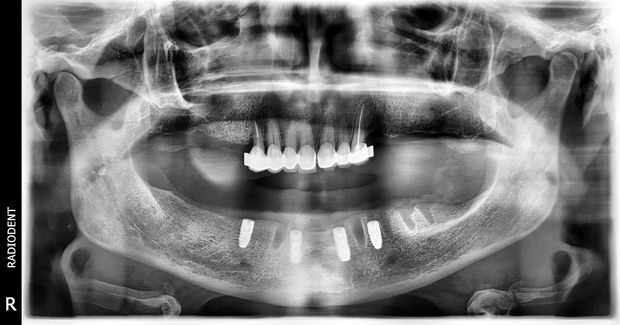

Uzupełnienie ruchome – proteza zakotwiczona na czterech implantach w żuchwie, idealne rozwiązanie dla pacjentów borykających się z problemem utrzymania protezy dolnej.